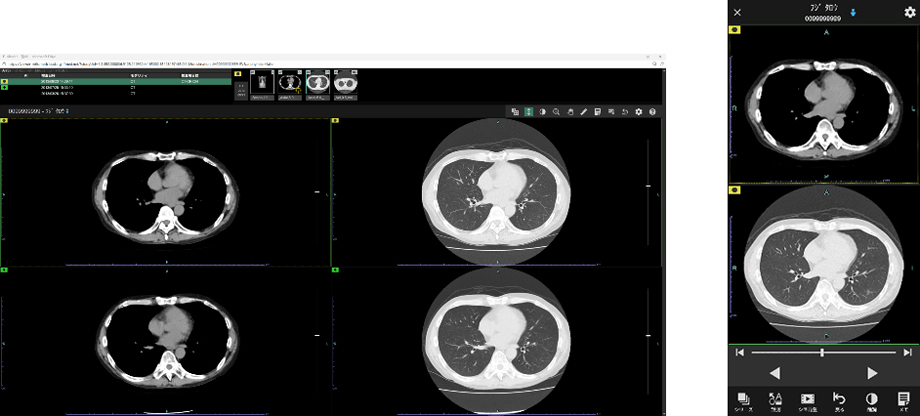

近年、CTやMRIなど画像診断機器の高度化により、医師が確認すべき画像枚数は増加している。「SYNAPASE LEAD Cloud」には、特定機能病院の7割以上で導入されている読影ビューワ「SYNAPSE SAI viewer」を標準ビューワとして採用した。「SYNAPSE SAI viewer」は高いカスタマイズ性を備えており、ユーザーの好みに応じて操作性や表示画面を柔軟に設定できる。画像配置を簡便に行える「レイアウティング機能」や、過去検査の画像と現在の画像を自動的に同期させる「自動スライス位置合わせ機能」など、多彩なワークフロー支援機能を搭載している。これにより、読影業務の効率化を図り、画像診断を強力にサポートする。

(3)いつでも、どこでも医用画像を参照できる「Cloud viewer」

「Cloud viewer」はPCやタブレットなどのモバイル端末を用いて、インターネット環境があれば、外出先や自宅、移動中でもCT、MRIなどの医用画像をスムーズに参照できるビューワである。専用ソフトのインストールは不要で、モバイル端末に標準搭載されているWebブラウザを利用し、端末に画像データを残さないゼロフットプリント方式を実現している。さらに「SYNAPSE SAI viewer」と操作性やユーザーインターフェースの共通性を追求することで、直感的な操作性を実現した。在宅診療・訪問診療など、クラウドならではの機動力を活かすことで、医療現場における医師の働き方改革に貢献する。